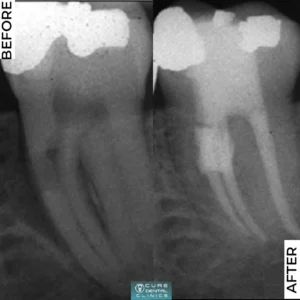

4- علاج عصب الأسنان

علاج جذر الأسنان بشكل يمنح الراحة التامة من الألم المصاحب له.

- كان المريض يشتكي من حساسية وألم شديد في الضرس وتم علاج عصب السن المتضرر وعمل حشو تجميلي له.